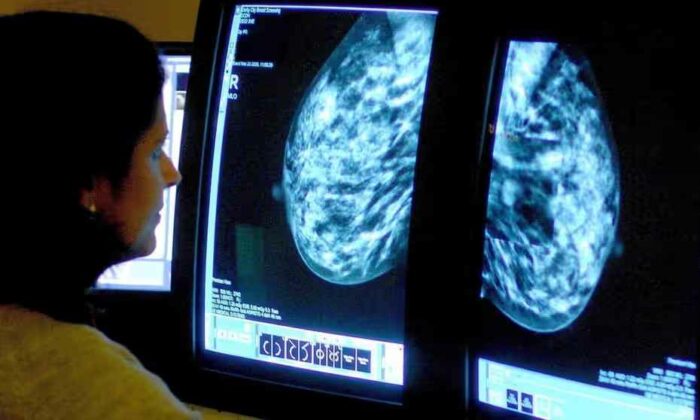

Telset.id, Jakarta – Sebuah studi baru dari jurnal Lancet Oncology telah menemukan bahwa penggunaan teknologi AI dapat membantu skrinning penyakit kanker mammogram.

Studi tersebut menemukan teknologi AI dapat dengan aman mengurangi beban kerja ahli radiologi, hingga hampir setengahnya tanpa ada risiko meningkatkan hasil positif palsu dari skrinning kanker.

Dari studi itu bisa dikatakan bahwa teknologi AI yang digunakan dalam skrinning penyakit kanker adalah setara dengan dua ahli radiologi yang sedang bekerja sama dalam mendeteksi penyakit tersebut.

Skrinning mamografi yang didukung teknologi AI menghasilkan tingkat deteksi kanker yang serupa dengan pembacaan ganda standar, dengan beban kerja pembacaa layar yang jauh lebih rendah, dan menunjukan bahwa AI aman digunakan dalam skrinning ini, menurut studi tersebut.